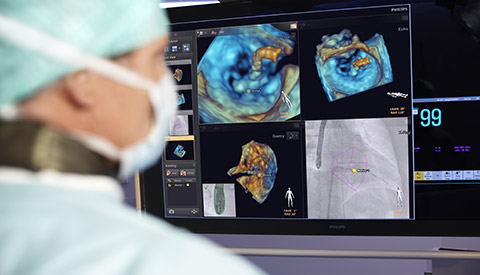

تم تشخيص أحد المرضى لديك بتضيّق في الصمام الأورطي المصحوب بأعراض. يبلغ عمر المريضة 85 عامًا وهي تعاني من السكري وارتفاع ضغط الدم. أنت تدرك خطورة وضعها الصحي ما يجعلها غير مناسبة لجراحة القلب ولكن يسمح لها بأن تكون مرشحة لاستبدال الصمام الأورطي باستخدام القسطرة (TAVR). في يومنا هذا، تمنح حلول التصوير المبتكرة والأجهزة التي تعمل عن طريق الجلد الأمل لبعض المرضى الذين لا تتوفر لهم حتى الآن أي خيارات علاجية أخرى.

تعلّم المزيد حول حلول طب القلب التي تقدمها شركتنا.